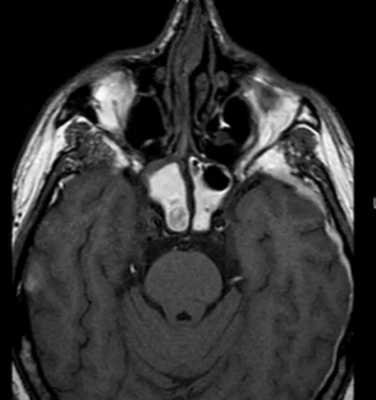

Больной Я., 22 лет, поступил в клинику с направляющим диагнозом: нагноившаяся атерома лобной области. При поступлении предъявлял жалобы на отек лица, наличие болезненного уплотнения в области лба. Из анамнеза: считает себя больным в течение 2 сут, когда без видимой причины отметил появление описанных выше жалоб. Данное заболевание - впервые, ранее никаких изменений в лобной области не отмечал. В детстве перенес ушиб области лба, за медицинской помощью не обращался. При поступлении общее состояние удовлетворительное. Температура тела 37 °С. В области лба слева на границе с волосистой частью головы имеется умеренно болезненный инфильтрат плотной консистенции размером 3×1,5 см, кожные покровы над ним не изменены. Симптом флюктуации отрицательный. Лабораторных признаков воспаления не выявлено. Так как на момент поступления убедительные данные, свидетельствующие о процессе, отсутствовали, начата антибактериальная, противовоспалительная терапия. Однако в ходе динамического наблюдения (в течение суток от момента госпитализации) отмечена отрицательная динамика со стороны местного статуса в виде прогрессирования воспалительных явлений, в связи с чем больной оперирован в экстренном порядке: под внутривенным наркозом произведено вскрытие гнойника. Интраоперационно выявлен подкожно расположенный гнойник объемом до 20 мл, в дне раны имелся дефект наружной костной пластинки лобной кости с неровными краями, лишенный надкостницы, диаметром до 2 см. Произведены биопсия кости и посев со стенок гнойника. Операция завершена санацией и дренированием раны салфетками, смоченными антисептическим раствором. С учетом интраоперационных данных в раннем послеоперационном периоде больному с целью уточнения диагноза выполнена компьютерная томография черепа (см. рисунок), Рисунок 1. Компьютерная томограмма черепа. а - сагиттальный срез: дефект лобной кости с деструкцией наружной и внутренней пластинок. Рисунок 1. Компьютерная томограмма черепа. б - фронтальный срез: остеомиелит лобной кости с разрушением наружной костной пластинки, абсцесс мягких тканей головы. Рисунок 1. Компьютерная томограмма черепа. в - горизонтальный срез: сквозной дефект лобной кости. Рисунок 1. Компьютерная томограмма черепа. г - фронтальный срез: деструкция лобной кости с разрушением внутренней костной пластинки. Рисунок 1. Компьютерная томограмма черепа. д - трехмерная реконструкция: сквозной дефект лобной кости. при которой выявлена деструкция лобной кости в виде сквозного костного дефекта размером 19×15 мм, что требовало проведения дифференциальной диагностики между остеомиелитом и новообразованием лобной кости. Выполнена сцинтиграфия скелета, при которой выявлен единственный очаг гиперфиксации радиофармпрепарата в лобной области слева. В ходе патогистологического исследования обнаружены кровоизлияния и признаки острого воспаления в костной ткани. Таким образом, на основании клинико-анамнестических, интраоперационных и ряда инструментальных данных у больного установлен диагноз гематогенного остеомиелита лобной кости, параоссального абсцесса. В послеоперационном периоде на фоне антибактериальной (с учетом данных антибиотикограммы), противовоспалительной терапии, местного лечения достигнута положительная динамика в течении раневого процесса, полностью ликвидированы воспалительные явления. Больной выписан под амбулаторное наблюдение хирургом с рекомендацией консультации нейрохирурга для решения вопроса о радикальном хирургическом лечении.

Приведено наблюдение острого гематогенного остеомиелита лобной кости у молодого человека, не отягощенного хроническими заболеваниями. Гематогенный характер патологического процесса установлен с помощью исключения других возможных путей попадания инфекции в кость. Клиническая картина заболевания не позволяла установить диагноз остеомиелита лобной кости в предоперационном периоде, однако и не соответствовала полностью локальному гнойному процессу в мягких тканях лобной области. В качестве дополнительного инструментального метода исследования с целью уточнения диагноза мы использовали компьютерную томографию, позволившую детально изучить изменения кости. Онкологическая настороженность потребовала выполнения также сцинтиграфии скелета и гистологического исследования. Комплексное консервативное лечение, проводимое в послеоперационном периоде, позволило добиться полной ликвидации воспалительных явлений и перехода раневого процесса во вторую фазу. Радикальное хирургическое лечение предпочтительнее выполнять в условиях отделения нейрохирургии при полном стихании воспалительного процесса, в связи с чем пациенту рекомендована консультация нейрохирурга.